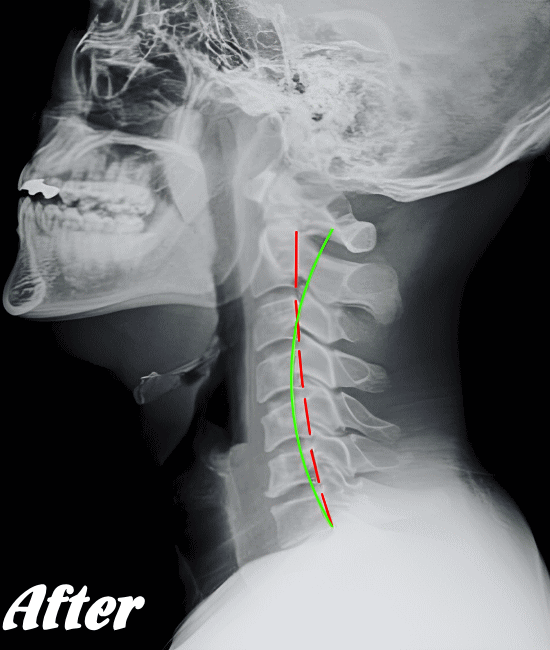

緊張型頭痛/肩こり頭痛の発生は、首背面の筋肉が緊張し血流が悪くなることが大きな原因だと考えられます。そこで、まずは首まわりや肩まわりの筋肉を緩め、潤滑な血行を確保させることを優先に施術します。

そのために、背骨の歪みを整え、肋骨、肩甲骨、首や首の付け根など、血流を阻害している部位の筋骨格をすべて調整します。